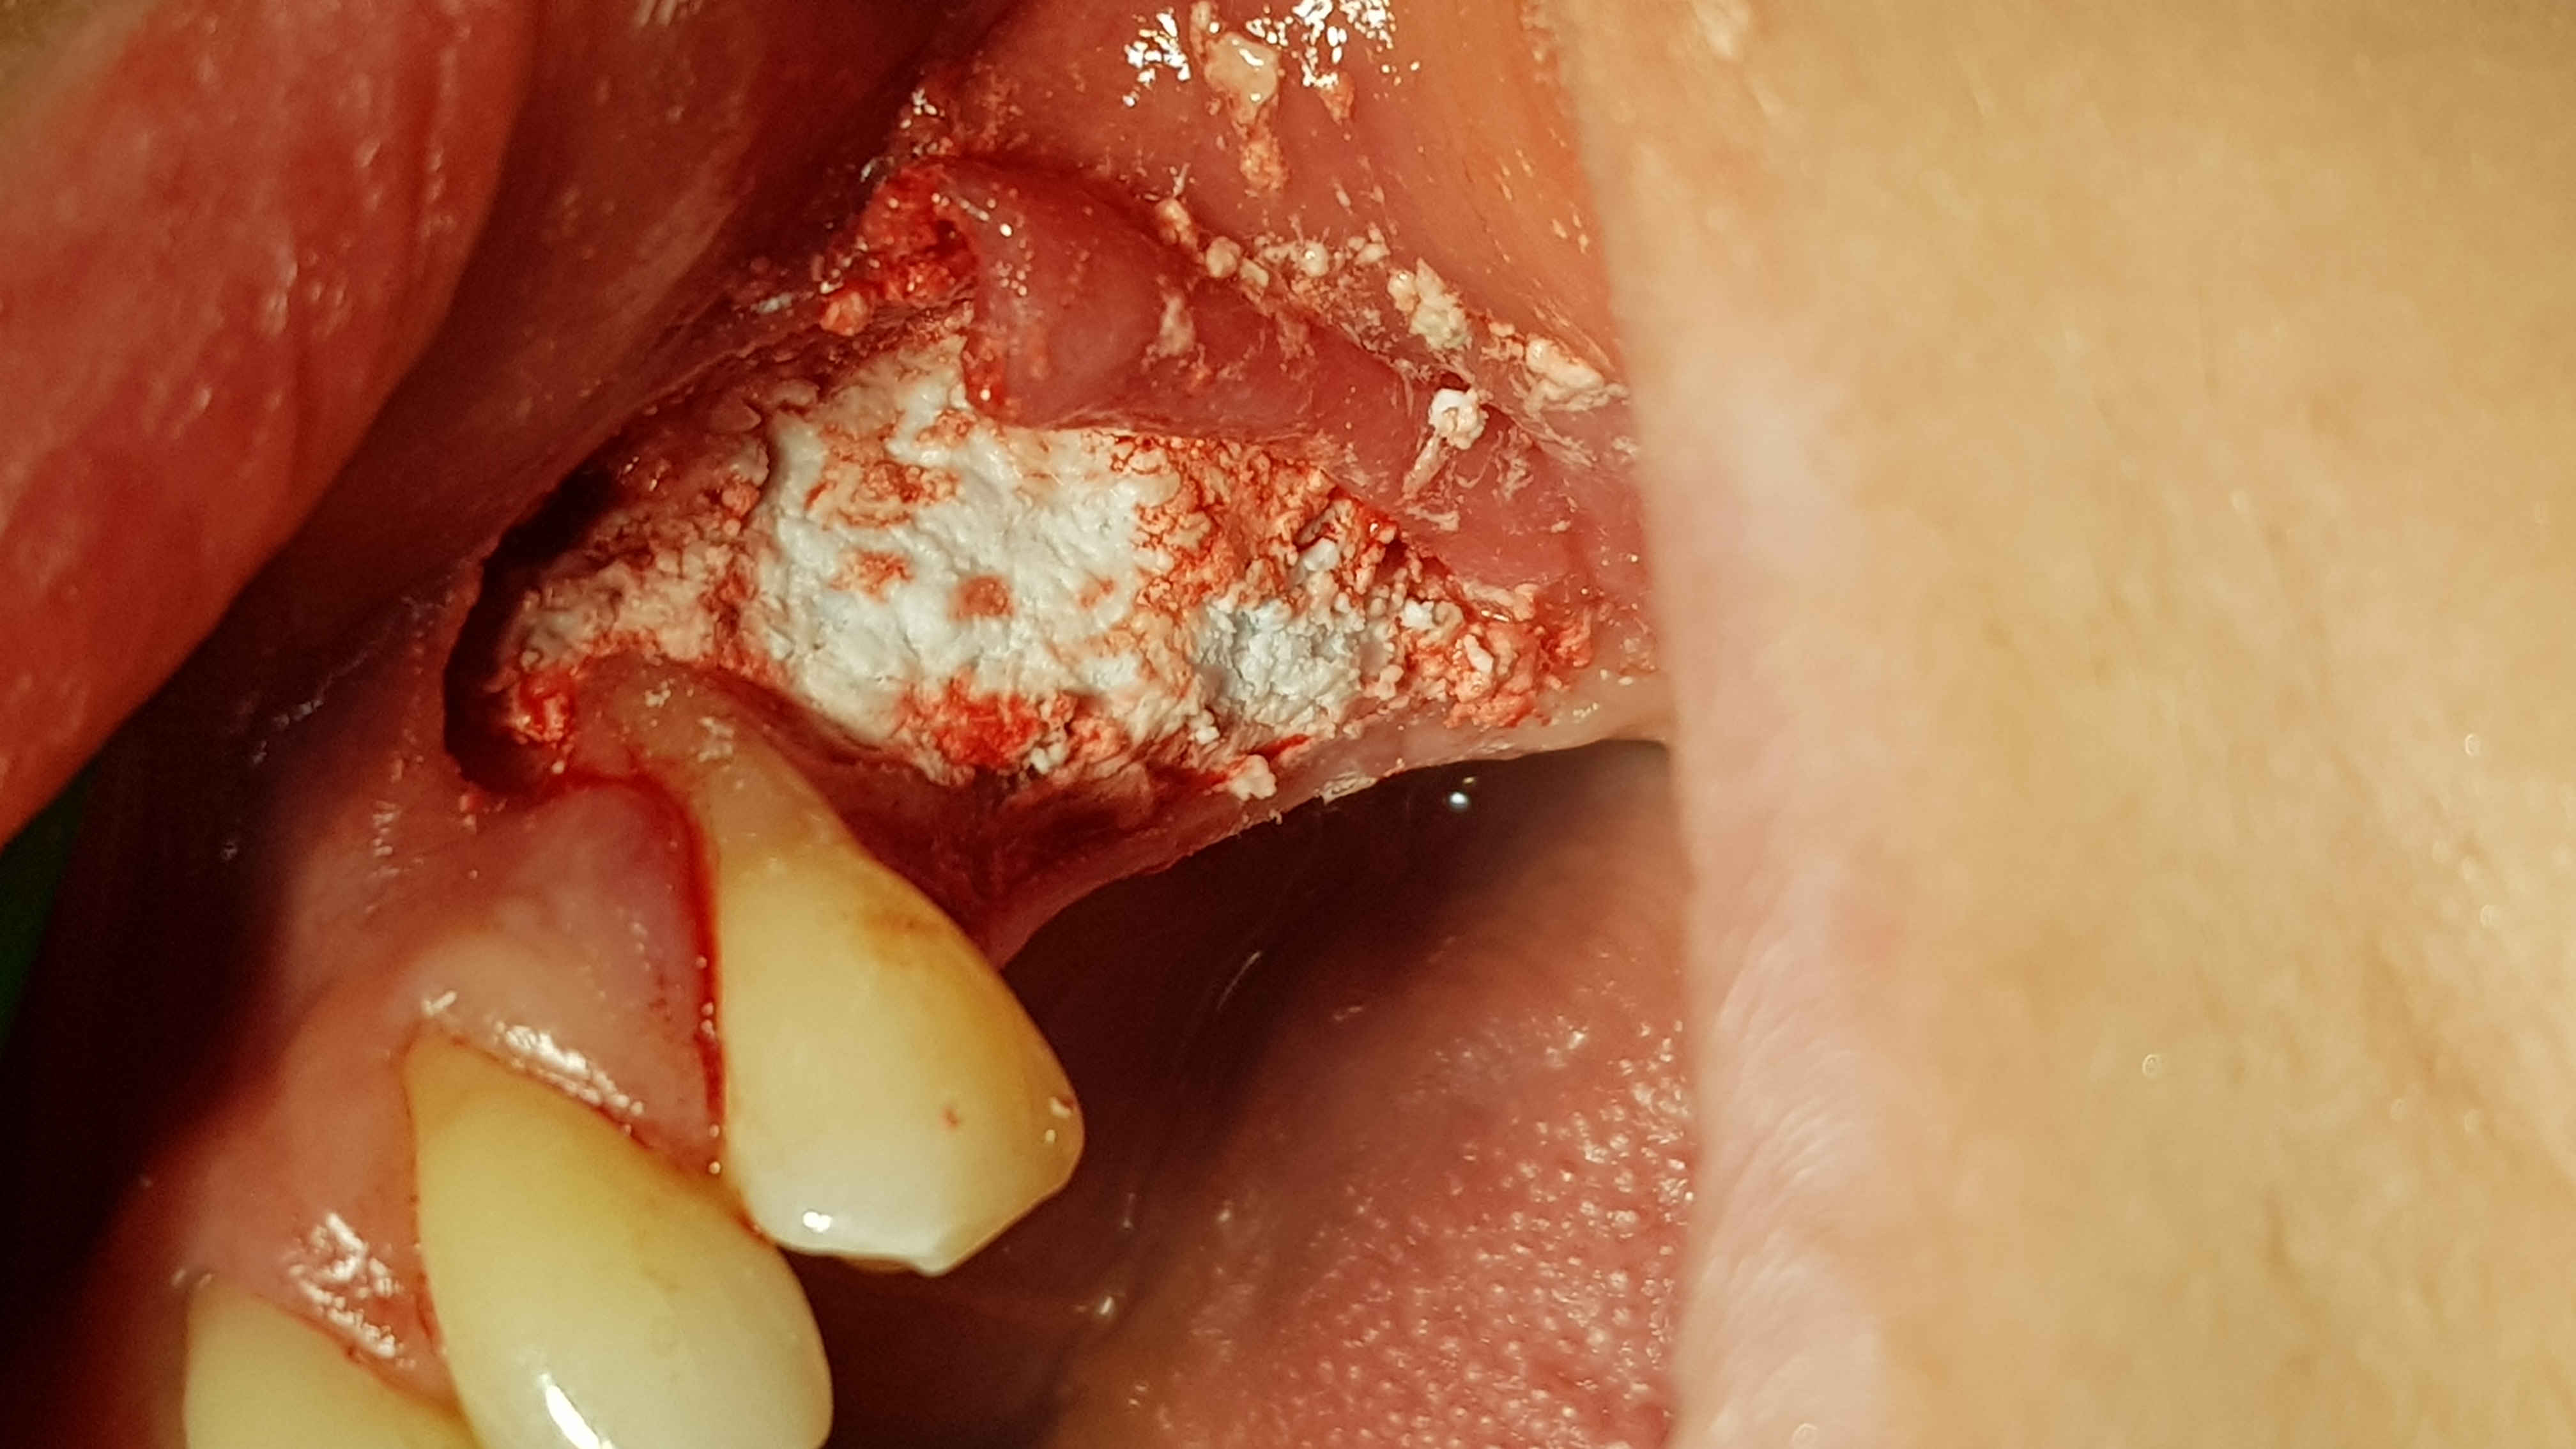

Wszystkie zabiegi przeprowadzono w znieczuleniu miejscowym 4% Artykainą z dodatkiem Noradrenaliny. W pierwszym etapie usunięto ząb 47. Stwierdzono częściowe uszkodzenia blaszki korowej przedsionkowej. Po opracowaniu rany ubytek wypełniono cementem regeneracyjnym (1 cm3) (ryc. 5).

Ryc. 5. RTg 7 dni po usunięciu 47 i augmentacji zębodołu